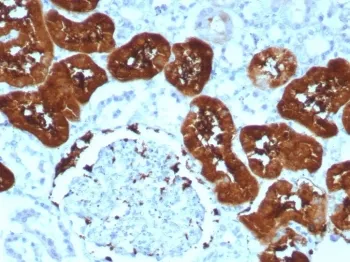

FABP1 Recombinant Antibody

- Applications: IHC-P